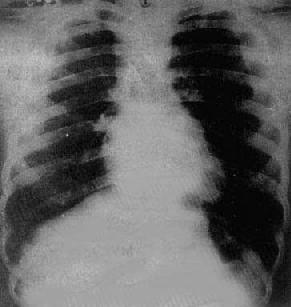

图3-2-17 慢性肺原性心脏病

心呈二尖瓣型,右心室增大,肺动脉突出,但无左心耳增大。肺动脉扩张,尤以右下肺动脉为明显,有肺门截断现象,说明有肺动脉高压。肺纹理增强,肺透明度增加,膈平而低,说明有慢性支气管炎和肺气肿

X线表现(图3-2-17)为肺动脉高压和肺部慢性病变的改变:①肺动脉高压,常出现于心形态改变前之前;②右心室增大,心呈二尖瓣型,心胸比率大于正常者不多,部分病例心比正常为小,与肺气肿、膈低位等因素有关。左心室如增大则常为心力衰竭所致。右心房增大少见,常由于右心室压力增高,右心房排血困难所致,右心房不增大;③肺部慢性病变,有慢性支气管炎,广泛肺组织纤维化及肺气肿等表现。